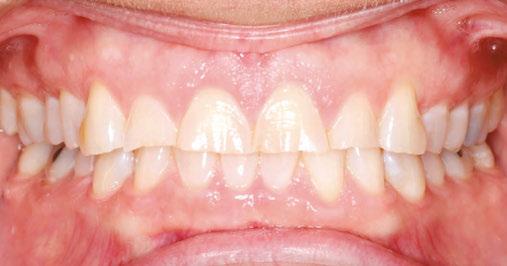

Figures 13-17: Final restorative photos

Gingival health was excellent, and her dentist was ready to move forward with veneers on teeth Nos. 7, 8, 9, and 10 shortly after that. A new maxillary Essix was fabricated when she had her temporary veneers, and a final maxillary clear Essix was delivered once her restorations were complete. She was instructed to wear the upper clear retainer to bed at night, and she will also be fit for a new maxillary flat-plane splint if her clenching and grinding continue. The patient’s awareness of her bruxing improved throughout treatment, and she has reduced her daytime clenching.

This case was completed in 14 months and likely would have been completed sooner if not for her occasional broken archwires. She was delighted with the esthetics and comfort of her clear brackets and is happy with her esthetic result. The Ormco Symetri Clear bracket system helps to increase case acceptance while giving the orthodontist the control and predictability required to finish complex restorative cases efficiently.